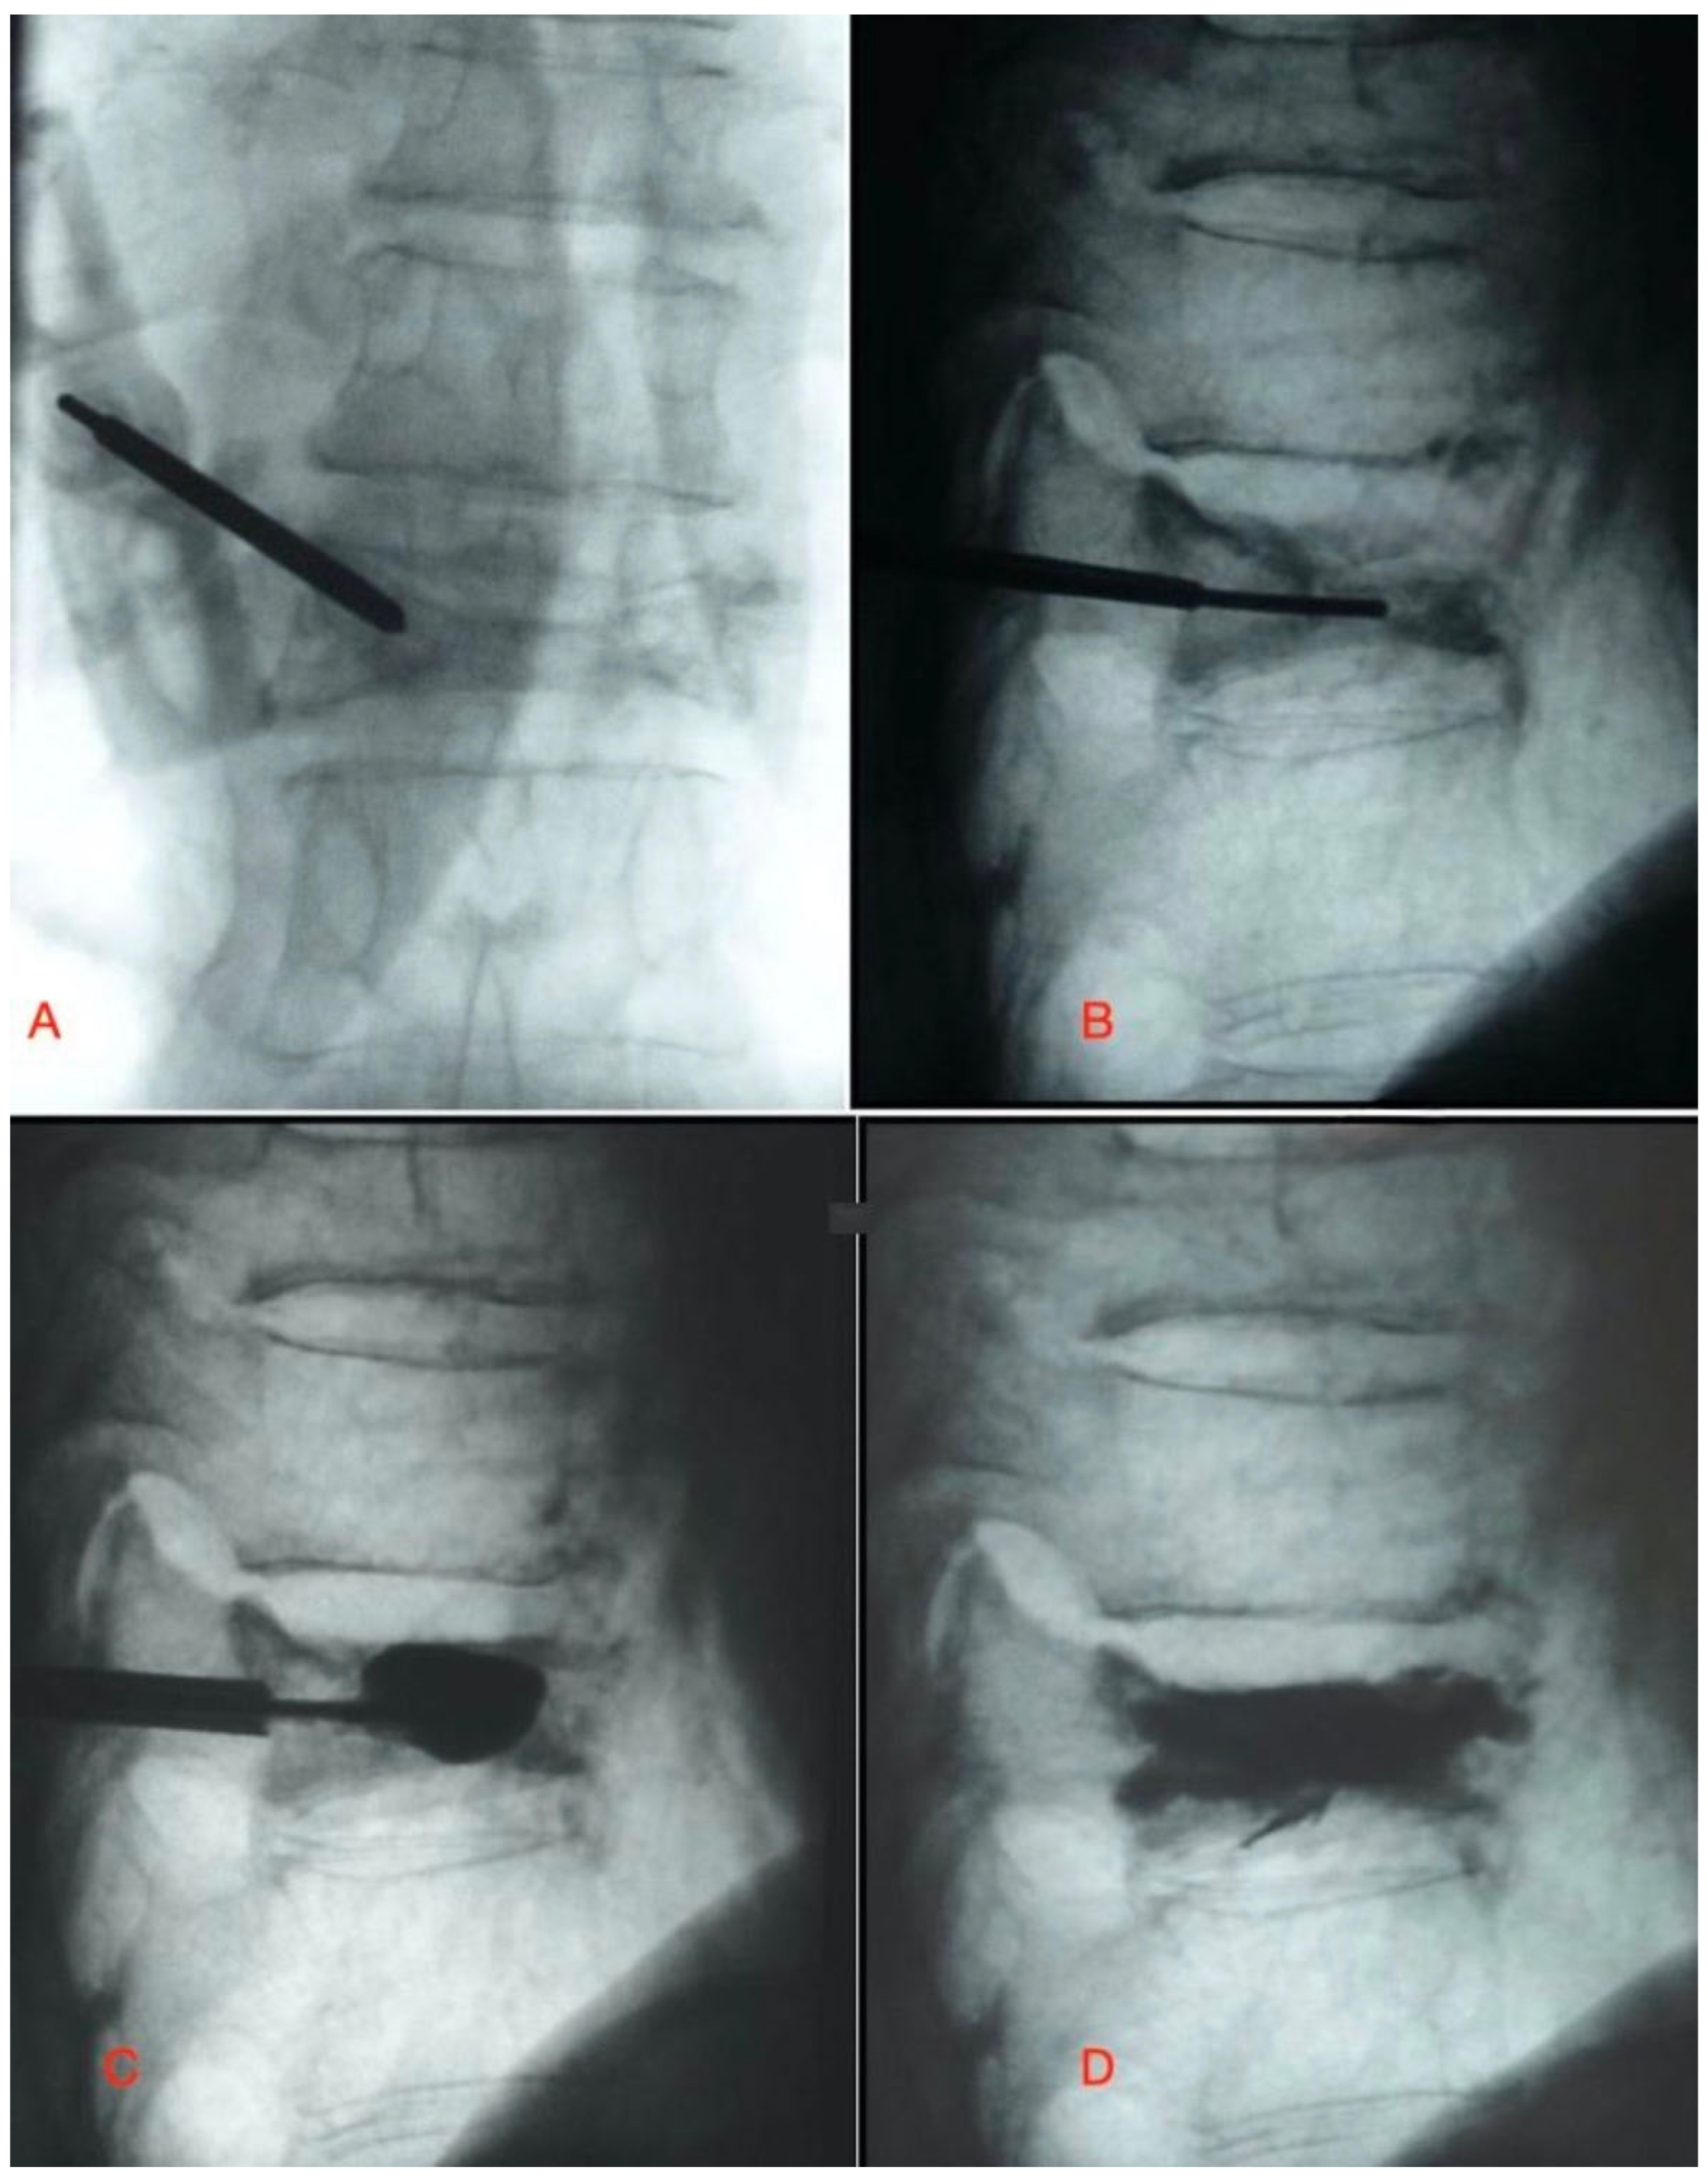

For radiological evaluation, all patient radiographs were retrieved from the hospital’s PACS (Picture Archiving and Communication System), and distance and angle measurements were performed digitally. Printed radiographs were not used due to the potential for magnification errors. The kyphosis angle (KA) (Figure 2) and the lowest anterior vertebral height of the fractured vertebra (Figure 3) were measured preoperatively, immediately postoperatively, at two years, and at three years, with the difference in healing rates calculated. The kyphosis angle (KA) was determined by measuring the intersection angle between lines parallel to the upper and lower end plates of the fractured vertebra. The lowest anterior vertebral body height was measured from the shortest region of the anterior vertebral wall. Postoperative vertebral height measurements were obtained from the same location on follow-up radiographs. Changes in kyphosis angle and anterior vertebral height were measured and are expressed as a proportion relative to the initial values.

Figure 2. Measuring the kyphotic angle. It was calculated as measuring the angles between lines running parallel to the upper and lower endplates of fractured vertebrae before and after surgery (A,B) (Sagittal MRI showing bone edema due to acute fracture).

Figure 3. Recovery of the vertebral height was measured by measuring the lowest vertebral height before and after surgery. (A) The arrow indicates the lowest vertebral height. (B) The arrow indicates the recovery of the vertebral height at the same location after surgery (Sagittal MRI showing bone edema due to acute fracture).